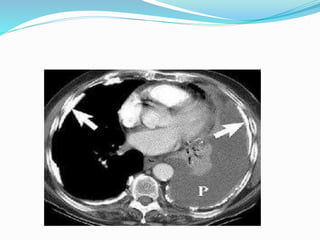

‫ورم‬

‫الريقة‬

‫المتوسطة‬

Mesothelioma

‫الجنبي‬

‫أو‬

‫البريتواني‬

 ‫الخاصة‬ ‫المضاعفات‬ ‫أهم‬ ‫باألميانت‬ :  ‫الرئة‬‫انتفاخ‬  ‫المزمن‬ ‫القصبات‬ ‫التهاب‬  ‫الرئة‬ ‫سرطان‬  ‫ورم‬ ‫الريقة‬ ‫المتوسطة‬ Mesothelioma ‫الجنبي‬ ‫أو‬ ‫البريتواني‬